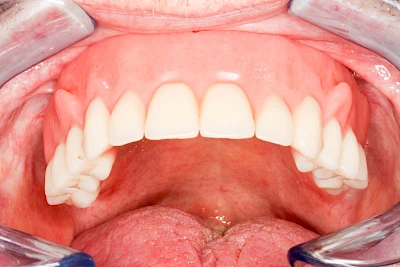

Fehlen einzelne Zähne und die Nachbarzähne sind unbeschadet oder gut zahnärztlich versorgt, werden immer häufiger Implantate gewählt, um die Lücken zu schließen. Auch bei größeren oder verteilten Lücken, wenn keine herausnehmbare Prothese gewünscht ist, werden Implantate für Kronen- bzw. Brückenversorgungen gesetzt. In Einzelfällen entscheiden sich sogar zahnlose Patienten für eine festsitzende Versorgung auf Implantaten.

Varianten zur Verankerung von festsitzendem Zahnersatz auf Implantaten